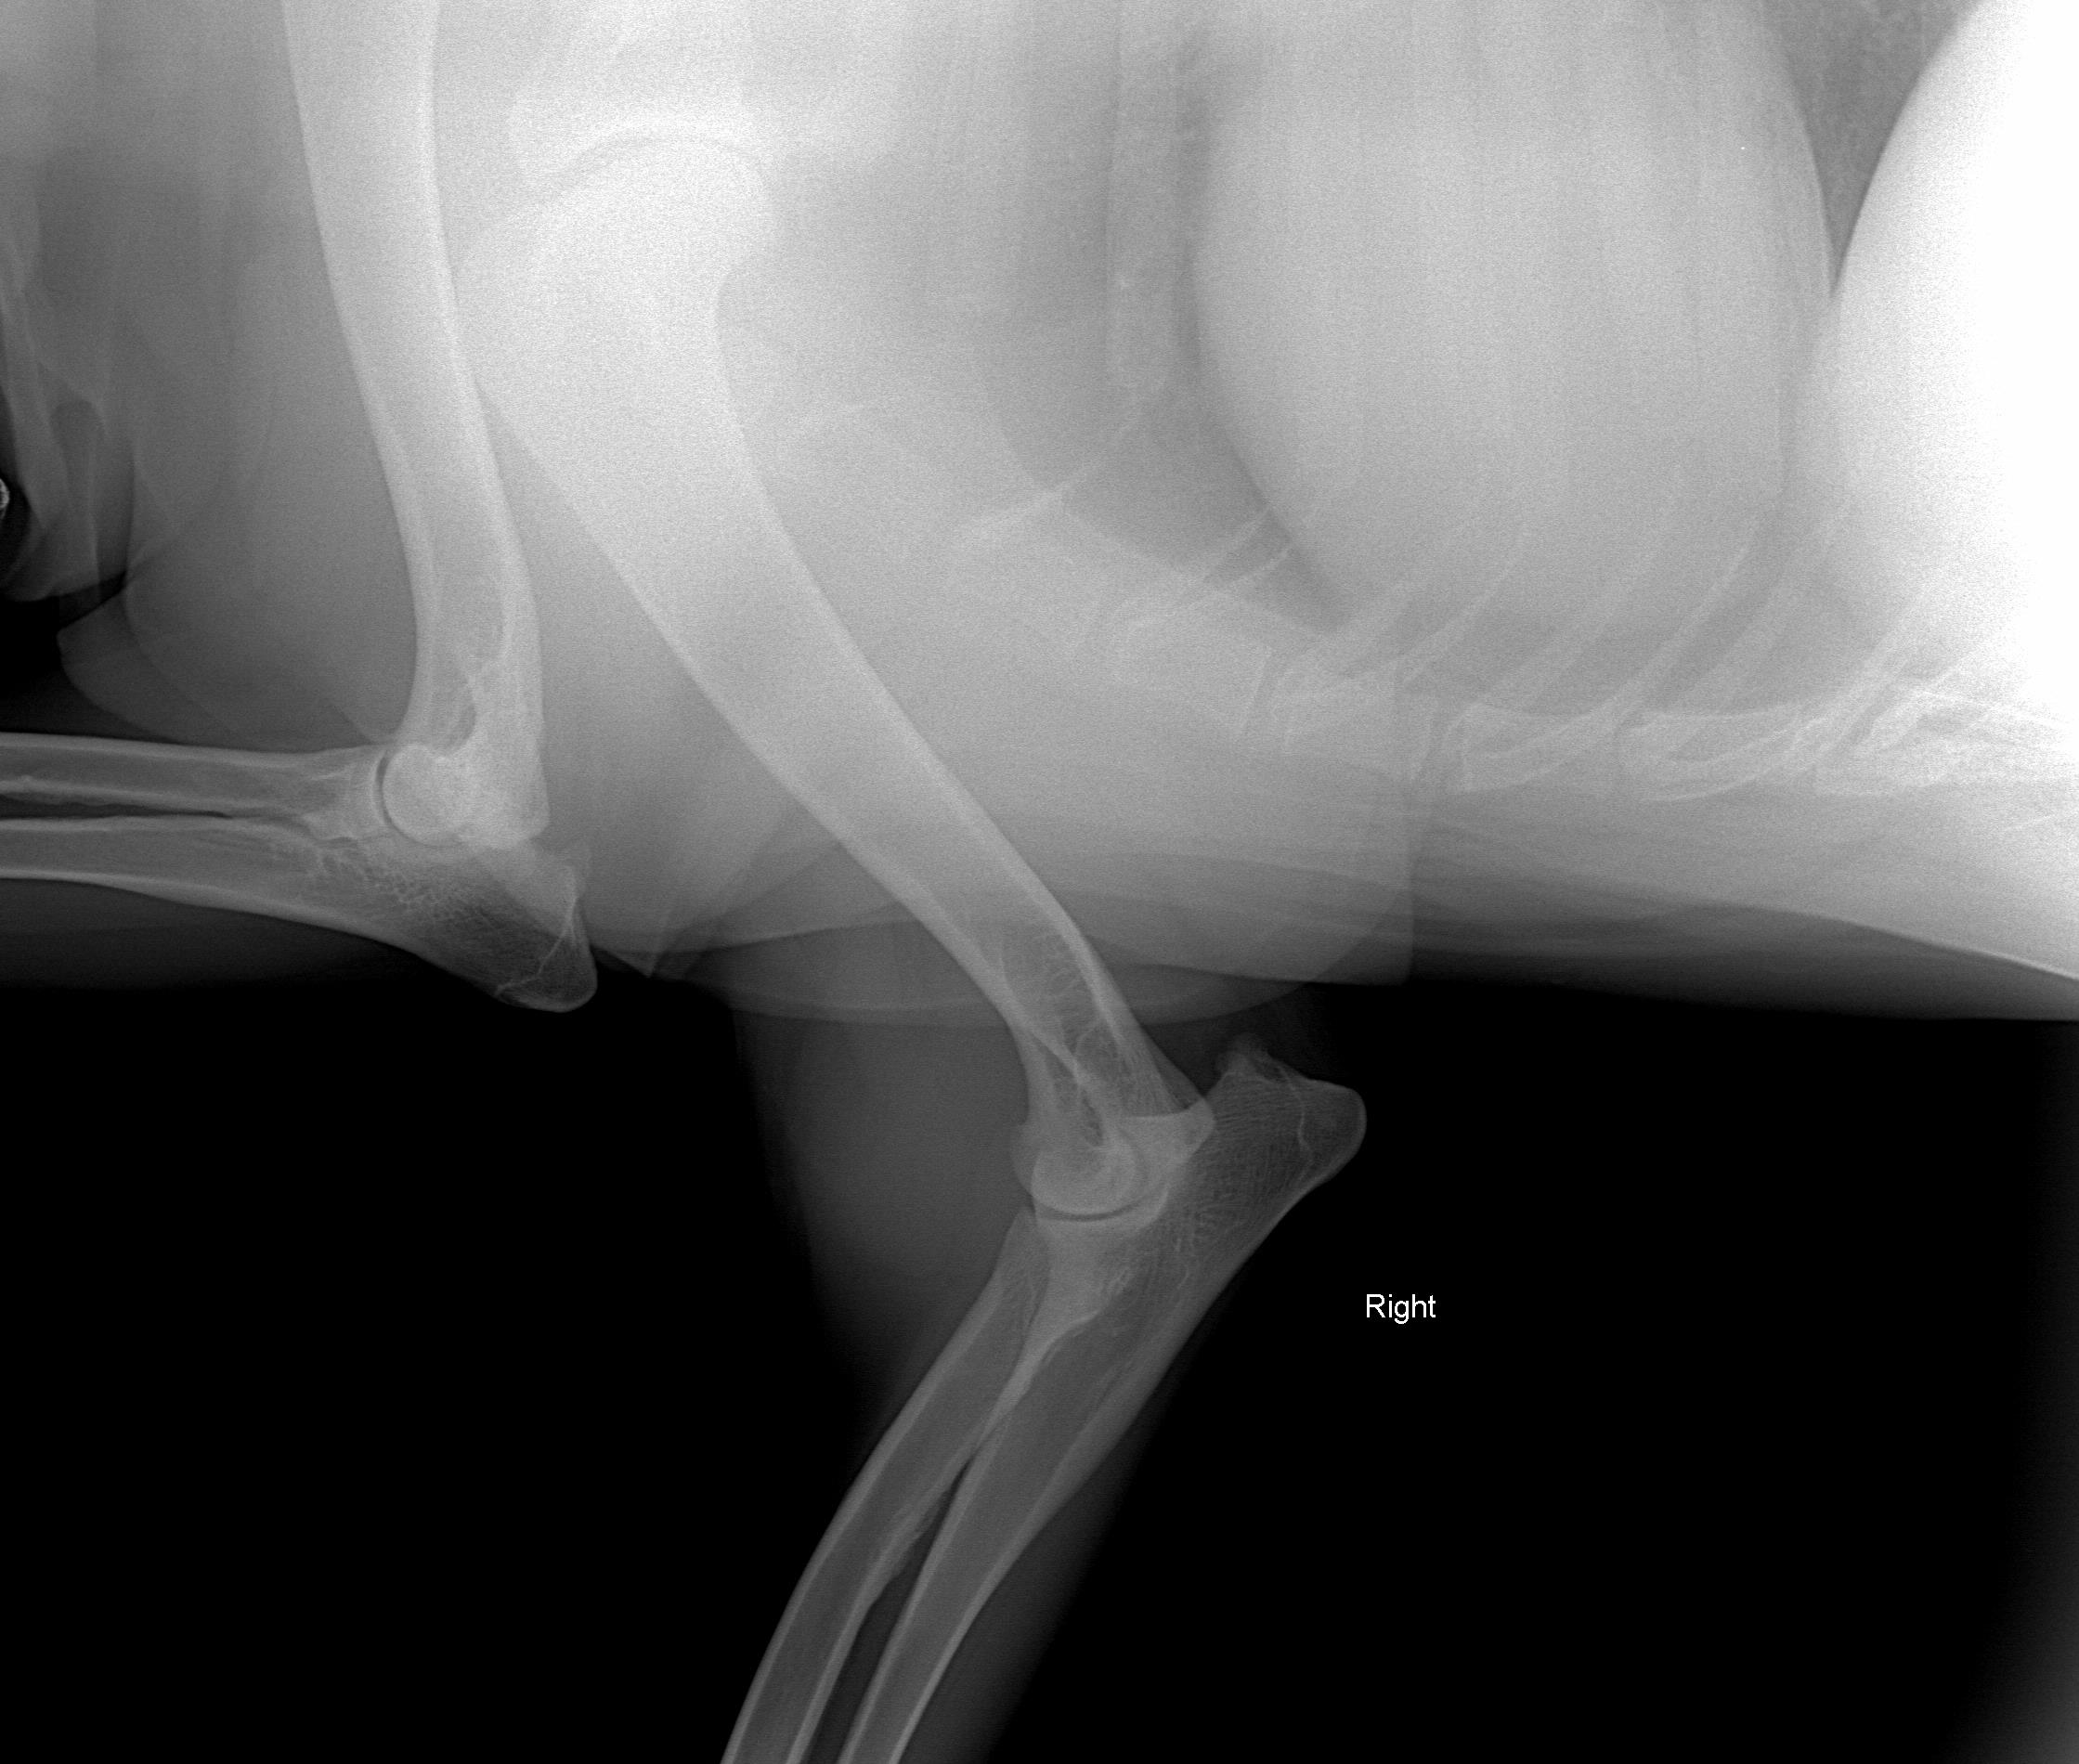

Things are not looking good. We have done three separate series of x-rays on three different days and using two different radiology labs with the most recent being 2-13-09. We have done at least two series of Fine Needle Aspirations with the results being inconclusive. This lump has moved from the outside of the elbow, to the inside and now is on top of the elbow. In January we had the lump down to the size of a walnut and limited to the top of the elbow. Now it has ballooned up to the size of a softball with only reducing slightly on any given day.

Picture taken August 17, 2008 - right leg - swelling to the outside. The swelling was to the outside.

Picture taken 1/24/09 - another lump has developed. The old lump was reduced to the size of a walnut with heat pack, physical therapy/massage (3x per day)

The following pictures are from last week 2/14/09.

On July 3, 2008, after Zoey finished her pig ear she was chasing her tail and caught the corner of the wall and never recovered from her injuries.The xray was taken 2/13/09

We consulted 5 vets, 3 series of x-rays, FNA twice and no one had ever seen anything like it before.

The following xrays were taken August 2008.